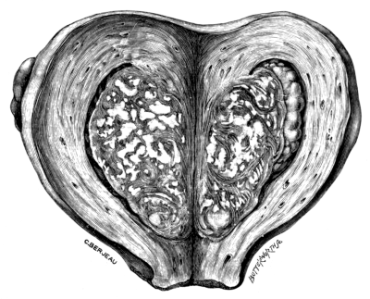

| 2. | Secondary Cancer of the Ovary in Section | 15 |